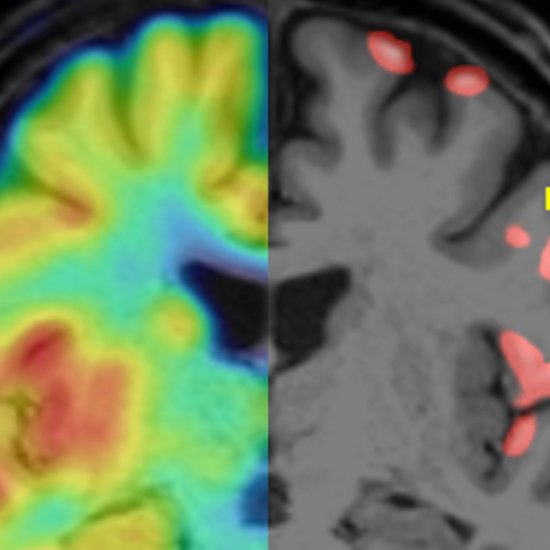

| | News • Bildgebung zeigt SynapsenverlustMultiple Sklerose greift unter anderem die graue Substanz im Gehirn an. Jetzt fanden Forscher mit PET-Bildgebung erstmals einen Weg, diese Schäden diagnostisch aussagekräftig abzubilden. |